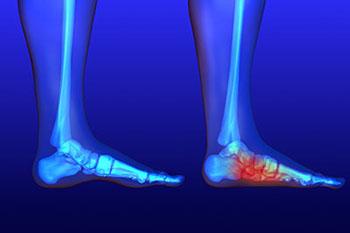

Flat feet is a condition that affects those who have little to no arch in their feet. When you stand, a person who doesn’t have flat feet will have a gap from the inner part of their feet to the floor, due to the normal arch that slightly rises off the ground. Those...